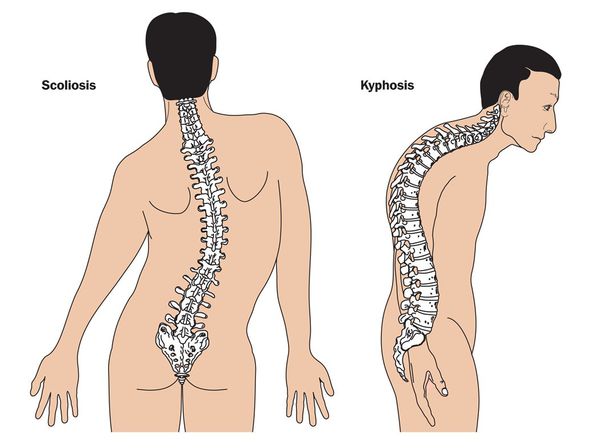

Sindrom marfana tema nauchnoj stati po klinicheskoj medicine chitajte besplatno tekst nauchno issledovatelskoj raboty v elektronnoj biblioteke kiberleninka (Тип файлу jpg)

Sindrom Marfana Tema Nauchnoj Stati Po Klinicheskoj Medicine Chitajte Besplatno Tekst Nauchno Issledovatelskoj Raboty V Elektronnoj Biblioteke Kiberleninka